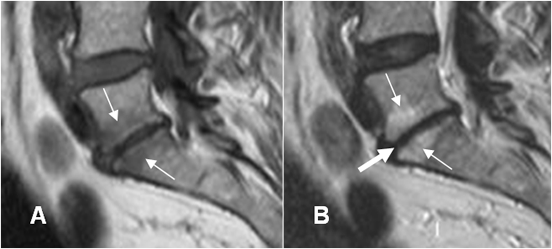

Fig 140 A. Espondilodisquitis.

A: RM axial en T1 y B: RM axial en T1 con contraste. Alteración en la señal del disco por proceso infeccioso, con masa de tejidos blandos, que realzan con el contraste.

Fig 140 B. Espondilodisquitis.

A: RM sagital en T1. Alteración en la señal del disco y las placas terminales, con masa de tejidos blandos que ocupa el canal.

B: RM sagital y C: RM axial en T1 con contraste. Realce oseo y de la masa de tejidos blandos, de forma homogénea, que corresponde a flemón y ocupa el espacio epidural.